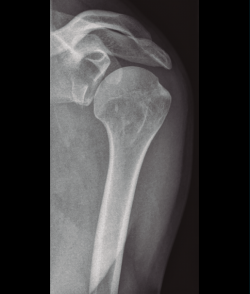

El examen radiológico debe consistir en radiologías simples de la clavícula y el hombro (Figura 2); también es recomendable una tomografía axial computarizada (TAC).

Existen distintos tipos de fracturas escapulares. En ocasiones, tras una fractura glenoidea (35%) (Figura 3), pueden producirse fracturas de coracoides (7%) (Figura 4) y también pueden ocurrir fracturas escapulares indirectas por caídas con la mano extendida(1,3,5).

Shekelle et al.(9) concluyen que no existe evidencia en cuanto a la elección del tipo de tratamiento, pero sí resulta de gran importancia individualizar el tratamiento valorando de forma integral al paciente, considerando el grado de desplazamiento, la densidad ósea, la edad y las lesiones asociadas (Figura 5).